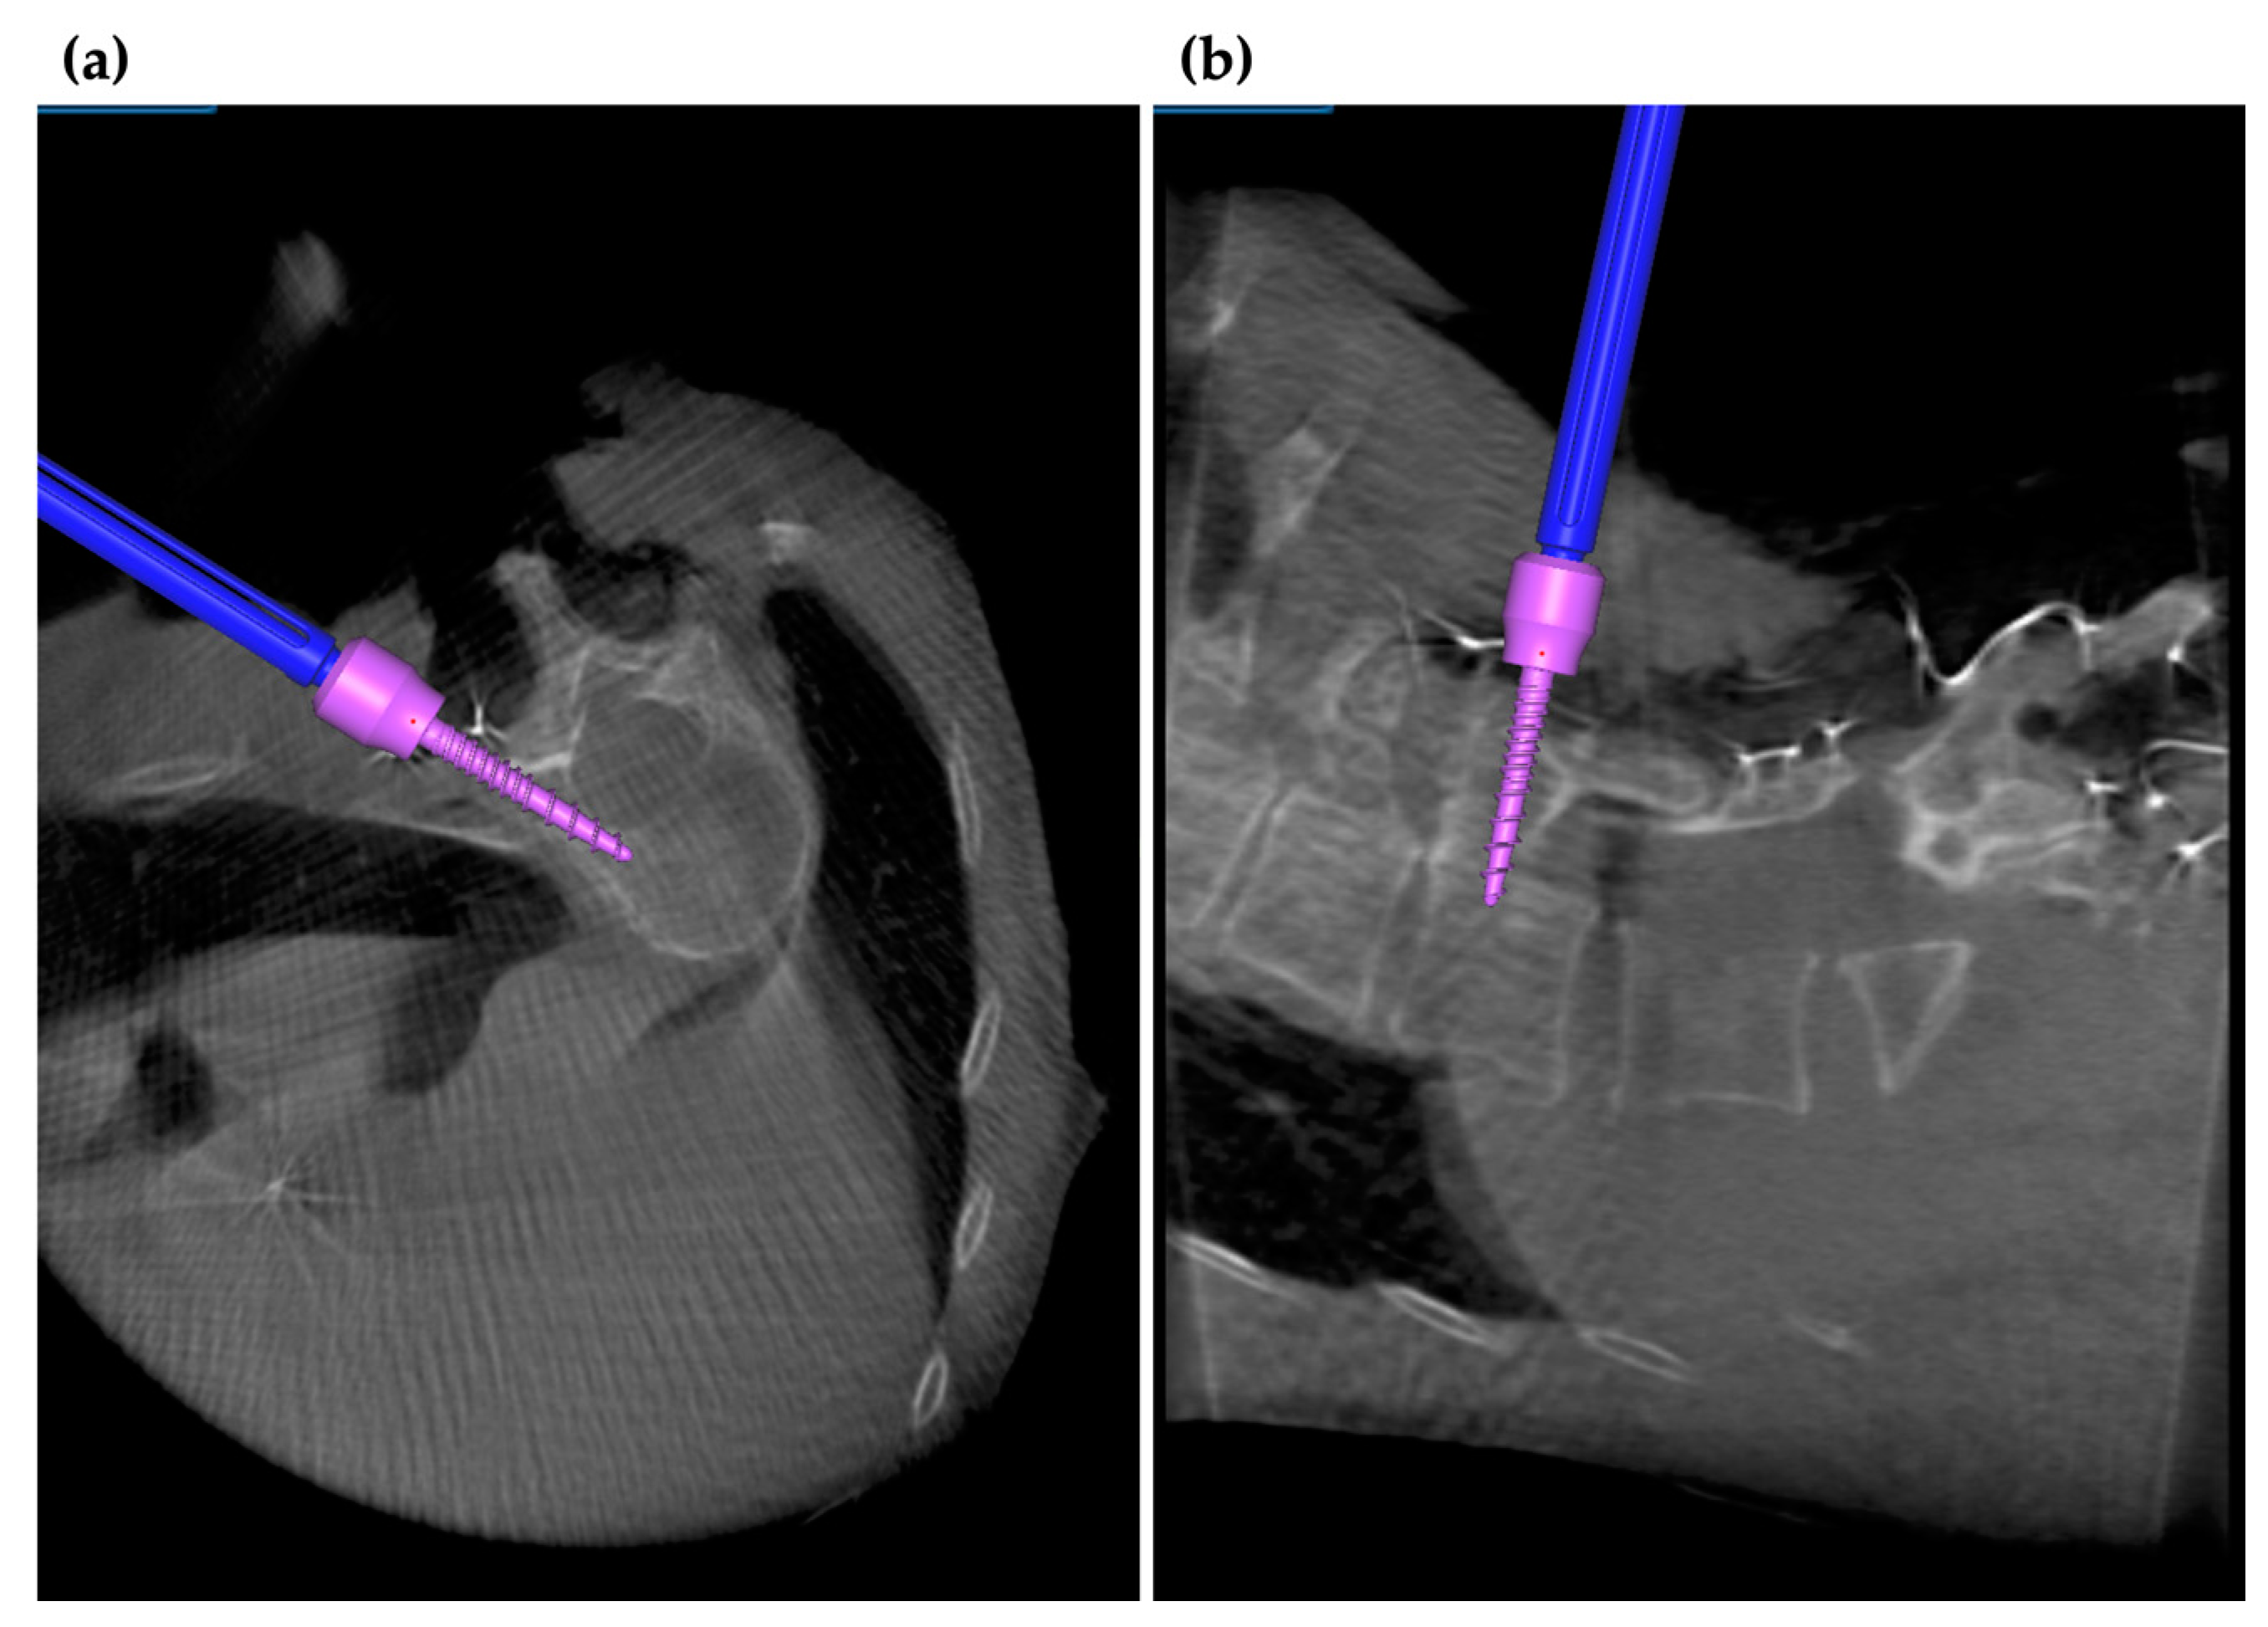

3.5. Application of Navigation System in MISt Procedures

3.6. Robotics-Assisted Surgery